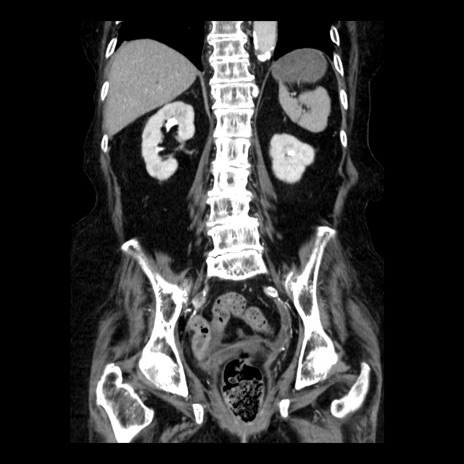

症例14(冠状断像)

【症例】 90歳代女性

【主訴】 腹痛・嘔吐

【現病歴】今朝から左側腹部痛を認めた。 経過観察していたが、嘔吐を認めたため来院。

【既往歴】 子宮癌術後

【身体所見】 意識清明、BP 127/54mmHg、P 98bpm Sp02 95%(RA)、BT 35.8°C、腹部平坦・軟腸ぜん動音聴取良好、右下腹部圧痛(+) 反跳痛なし

【データ】WBC 9800、CRP 0.46